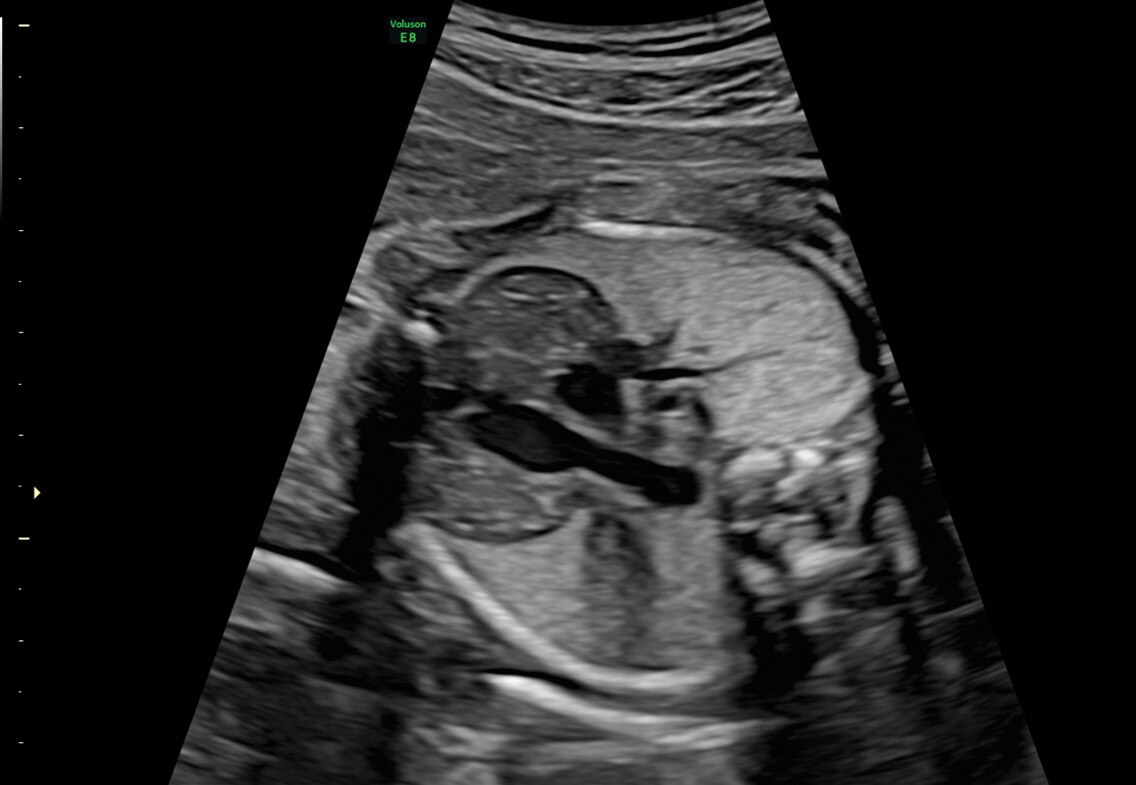

Voluson E8

O sistema de ultrassom Voluson™ E8 foi concebido para acompanhar o ritmo das clínicas com muito movimento, controlando com facilidade e precisão a rotina e os exames complexos de saúde das mulheres. A qualidade de imagem premium do Voluson E8 combinada com o acesso a recursos avançados oferece o nível de desempenho que você e seus pacientes exigem.